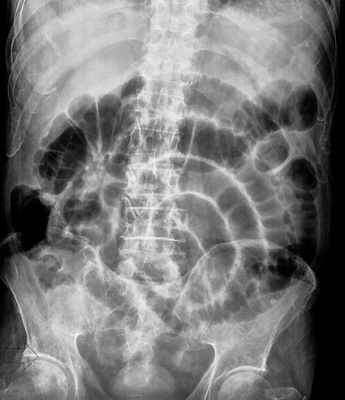

На рентгенограммах, полученных в положении стоя или лежа на боку, обычно видны горизонтальные уровни жидкости и газа (рис. 2). Рисунок 2. Обзорная рентгенограмма брюшной полости. Видны чаши Клойбера, уровни жидкости. Заполненные газом кишечные петли имеют вид опрокинутых чаш (чаши Клойбера). Они появляются при странгуляции через 1-2 ч после начала заболевания, при обтурации - через 3-5 ч. По размерам чаш Клойбера, их форме и локализации можно судить об уровне непроходимости.

При тонкокишечной непроходимости чаши Клойбера небольших размеров, ширина горизонтального уровня жидкости больше, чем высота столба газа над ним. Обычно наблюдается большое количество горизонтальных уровней с изменением их расположения в течение времени и перемещением жидкости из одной петли в другую. Горизонтальные уровни жидкости ровные. На фоне газа хорошо видны складки слизистой оболочки (складки Керкринга), принимающие форму растянутой спирали.

При непроходимости тощей кишки горизонтальные уровни жидкости локализуются в левом подреберье и эпигастральной области. При непроходимости в терминальном отделе подвздошной кишки уровни жидкости расположены в области мезогастрия.

При тонкокишечной непроходимости, кроме чаш Клойбера, на рентгенограммах видны растянутые газом кишечные петли, принимающие форму «аркад» или «органных труб», похожих на перевернутые буквы J и U.

При толстокишечной непроходимости горизонтальные уровни жидкости расположены по периферии брюшной полости, в боковых отделах живота, и их меньше, чем при тонкокишечной непроходимости. Высота чаш Клойбера преобладает над шириной. На фоне газа видны полулунные складки слизистой оболочки («гаустры»). Уровни жидкости не имеют ровной поверхности («зеркала»), что обусловлено наличием в толстой кишке плотных кусочков кала, плавающих на поверхности жидкого кишечного содержимого.

B ранней стадии непроходимости на обзорных рентгенограммах в положении лёжа будут видны умеренно pаздутые петли тонкой кишки с небольшим содержанием воздуха. При съёмке в положении стоя или на левом боку определяются множественныe уровни газ-жидкость. Складки Керкринга на ранних стадиях видны, по мере прогрессирования обструкции петли растягиваются и складки смазываются. Иногда очень сложно отличить раздутые петли тонкой кишки от толстой.

Обзорная рентгенография живота в положении стоя

Обзорная рентгенография живота в положении лёжа